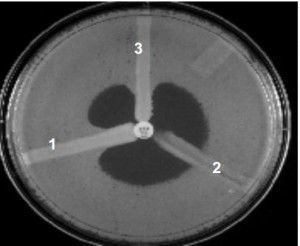

It is based on the inactivation of a carbapenem by carbapenemase-producing strains (test isolate) that enable a carbapenem-susceptible indicator strain (E. coli ATCC® 25922)  to extend growth towards a carbapenem-containing disc along with the streak of inoculum of the test strain. Positive test result gives cloverleaf-like indentation.

After 16–24 hours of incubation, examine the plate for a clover leaf-type indentation at the intersection of the test organism and the E. coli 25922, within the zone of inhibition of the carbapenem susceptibility disk.

A. MHT Positive test has a clover leaf-like indentation of the E.coli 25922 growing along the test organism growth streak within the disk diffusion zone.A positive test indicates carbapenemase production by the test microorganism. By producing carbapenemase, the test microorganism is able to inactivate the carbapenem that diffuses from the disk after the disk has been placed on the MHA. This allows carbapenem susceptible E. coli ATCC® 25922™  to grow toward the disk.

B. MHT Negative test has no growth of the E.coli25922 along the test organism growth streak within the disc diffusion zone.